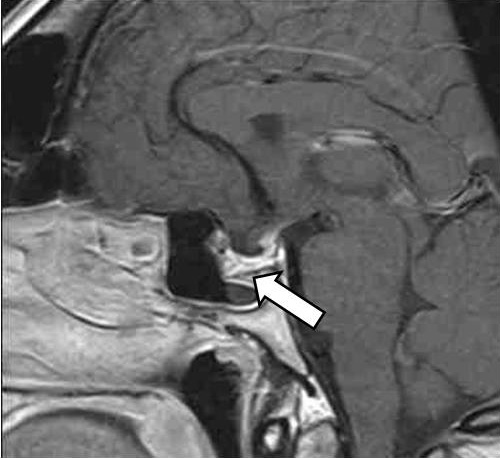

Клиническое наблюдение

Рис. 1. Магнитно-резонансная томография гипофиза с контрастным усилением, Т1-взвешенные изображения. Визуализируется макроаденома гипофиза с супра-, инфра-, латероселлярным ростом с кровоизлиянием (указана стрелкой)